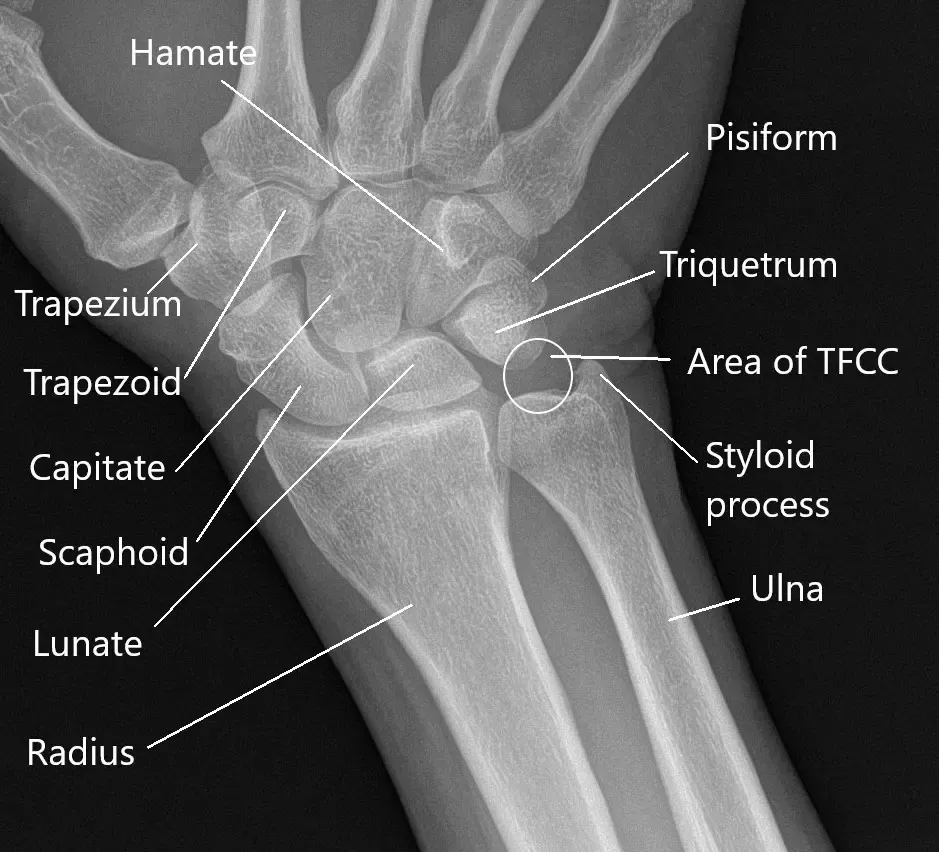

La articulación de la muñeca está formada por varias pequeñas articulaciones que conectan el antebrazo con la mano. Hay 8 huesos en cada muñeca que conectan con los huesos de la parte inferior del antebrazo y la mano. Además de los huesos, hay tendones y ligamentos que forman una parte esencial de la articulación de la muñeca. Diversas estructuras, como nervios y vasos sanguíneos, atraviesan la articulación de la muñeca en un espacio pequeño.

- El complejo de fibrocartílago triangular (TFCC) es un tejido pequeño que proporciona un amortiguamiento a los huesos pequeños del lado del meñique. Los desgarros de TFCC pueden causar dolor crónico e inestabilidad.

Generalmente se realiza un examen radiológico. Una radiografía ayuda a localizar fracturas y signos de artritis. Una tomografía computarizada es útil para buscar fracturas que no sean visibles en una radiografía. La resonancia magnética ayuda a detectar inflamación e hinchazón en la muñeca, así como las atrapamientos nerviosos.